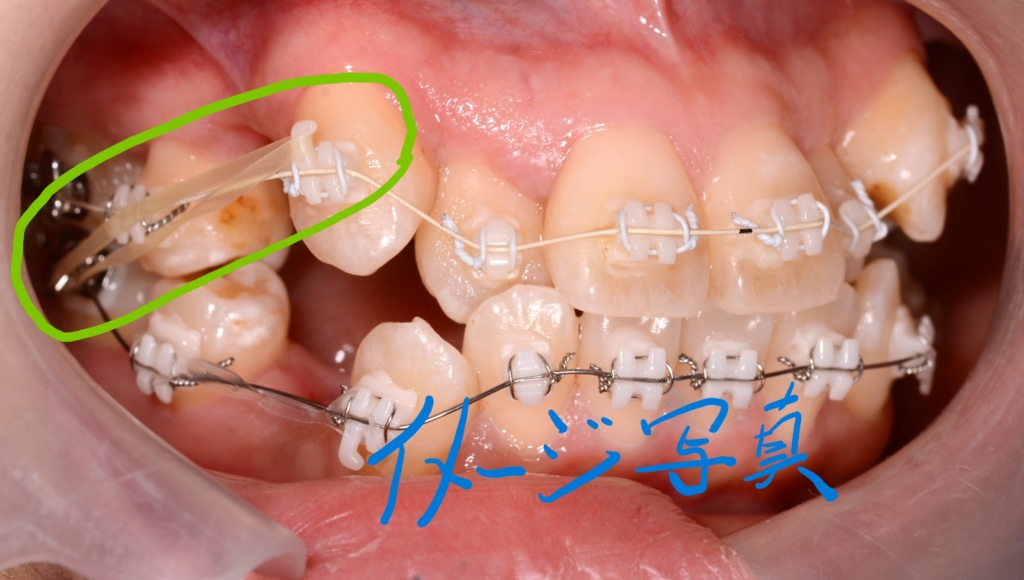

元々、左上は2本抜歯しなければいけないかも・・・という想定があり、想定通りになったかなという状況でした。 やはり「追加の抜歯はしたくない!」とのこと。

口蓋へのアンカースクリューも提案しましたが、「アンカースクリューは怖いし・・・」

ということで、従来法による顎間ゴムを併用することで可及的な改善を図る!という計画で進めることにしました。

緑色の丸で囲んだ中にある「下の奥歯から上の前歯にかかる矯正用のゴム」が顎間ゴムです